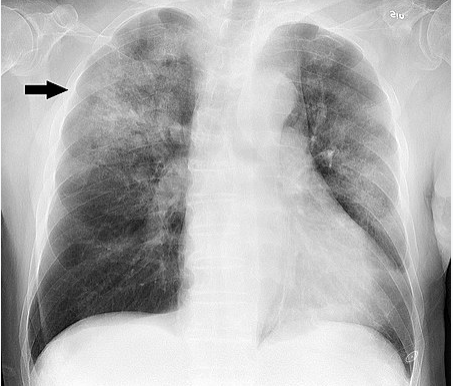

- 감염성 질환의 한 종류인 폐렴은 폐에서 발생하는 것으로 주요한 원인으로는 미생물에 의한 감염으로 발생하거나 세균이나 바이러스에 의한 감염도 폐렴의 원인이 됩니다.

-폐렴은 크게 신체적 증상과 호흡곤란, 호흡기 및 신체 기능 심각한 오염을 유발할 수 있는 원인으로 분류됩니다.

- 일반적인 폐렴 증상은 발열, 고열, 기침(가래가 동반된 습기가 있는 기침), 흉통, 호흡곤란, 혼돈, 어지러움, 무기력, 저작된 기력 등입니다. 각각의 원인별로 폐렴의 경과 및 치료가 달라질 수 있으므로 증상이 나타났다면 담당 의료진에게 상담이 필요합니다.